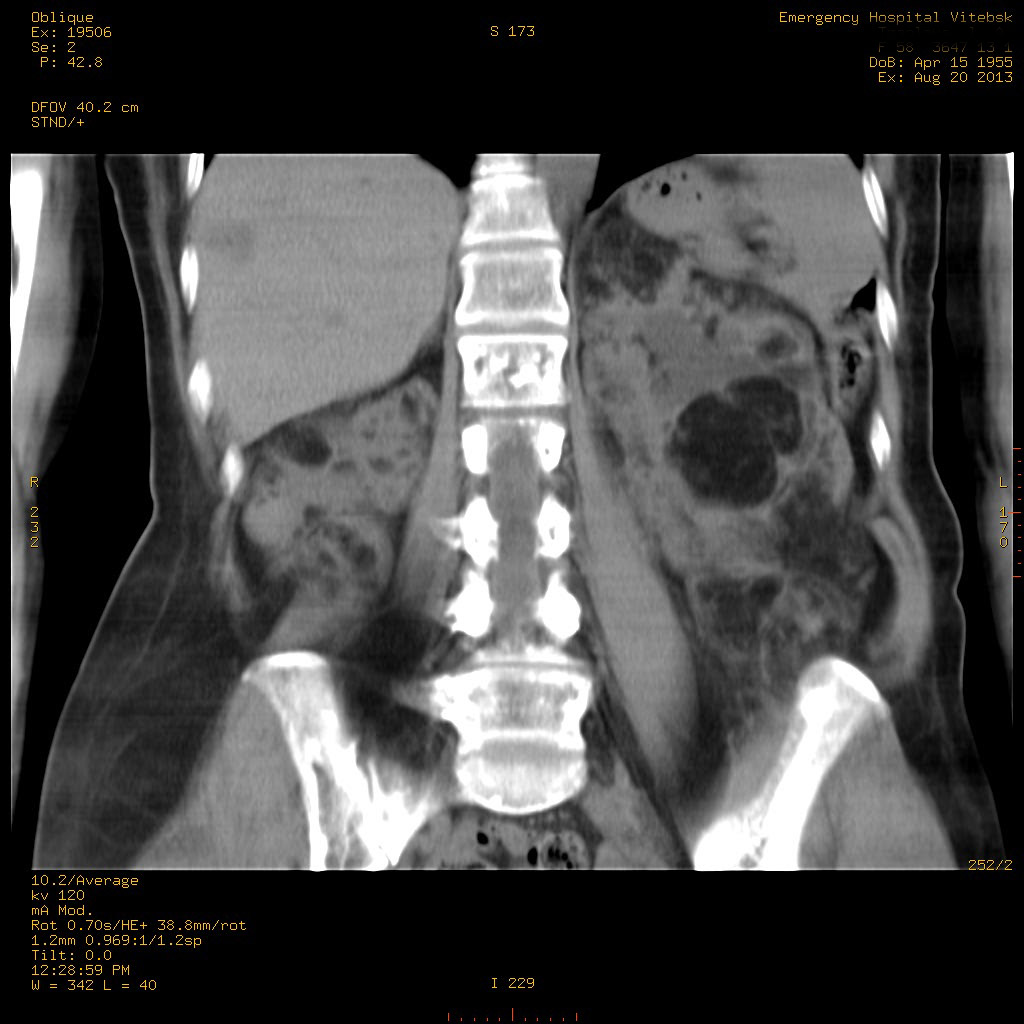

УЗИ почек - туберозный склероз

Пожилая женщина с нормальными мочевиной и креатинином.

Ангиомиолипоматоз почек , думаю компонент туберозного склероза.

Да, туберозный склероз.

Случай консультирован на кафедре радиологии Католического университета г.Лёвен (Бельгия) - зав каф. профессор Р.Оуен.